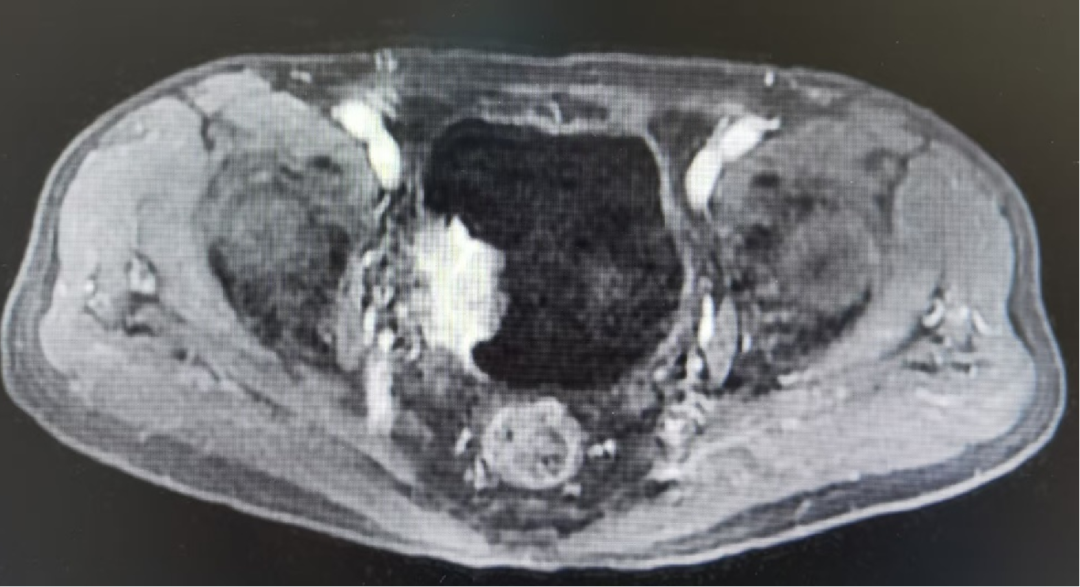

教授团队近期完成的一例高难度保膀胱手术,为这类患者带来了新的希望。肿瘤不仅侵犯膀胱肌层,更累及右侧输尿管壁内段,传统上几乎必然选择根治性切除。但患者保膀胱意愿强烈,影像学提示为局限性MIBC,团队决定迎难而上,开展经尿道保膀胱手术。医脉通特邀孙圣坤教授,为我们深入解析该病例的全过程,并展示关键手术视频,以飨读者。

肿瘤不仅侵犯膀胱肌层,更累及了右侧输尿管壁内段。传统的处理方式是行膀胱根治性切除术。但患者保膀胱意愿强烈,MRI检查提示为局限性MIBC,试行经尿道保膀胱手术。